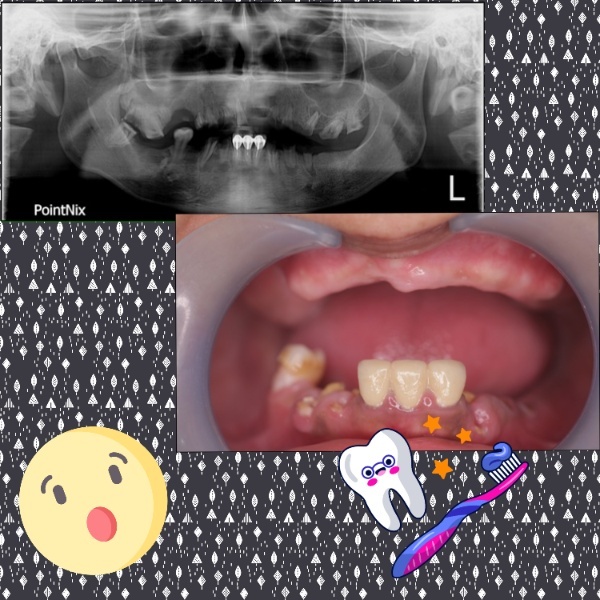

植牙專科醫師評估時發現媽媽有牙周病,拍攝X光片後,醫師針對牙周病部分有特別說明,媽媽因為牙周病導致牙床、牙肉、骨頭漸漸流失,在這樣的情況之下,必須先完成牙周病治療、齒槽骨重建、補肉補骨手術,接著才能進行全口重建,檢查當天植牙專科醫師詳細描述所有全口重建治療細節,也親切詢問媽媽過去身體健康及病史,就是希望在全口重建時能提升重建良率,成功完成所有治療。

媽媽年屆70好幾,雖然口腔牙齒所剩無幾,離院前植牙醫師主動幫媽媽仔細清潔牙齒,還特別宣導衛服部現在有老人塗氟服務,貼心幫媽媽順道塗氟保護僅剩的牙齒。

在新全美牙醫師專業技術,媽媽牙周狀況終於已經可以施做全口重建~~